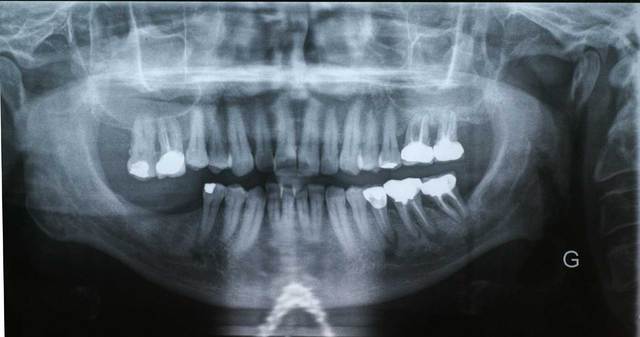

Bon, tirés de ma collection perso quelques petites panos avec des cas où vous pourrez vous en donner à coeur joie sur savoir ce qu'il faut faire (les deux patients sont un chauffeur de bus et l'autre retraité de la mairie)

Selon les endroits de ce pays , les quartiers de certaines villes ce n'est pas le pano le plus choquant qu'il y ai lieu de voir. Quel type de patient est ce, son allure genral ,sa façon de s'exprimer etc....Vous allez pensez que je fais du Sarkozysme mais non. Il y a donc un probleme initial du à l'éducation du patient dans son jeune age (et oui la France et sa politique de prevention qui fait que tous les français de 18 à 99 ans ont au moins un 6 pourrie!!!) et ensuite les chir dent entre lesquels il est passé.

J'ai peur que si tu remet tout à plat pour un trt global le patient prenne peur (non pas seulement au niveau fiancier) mais pense que ce qu'il a soit grave et là il fera un deni ....et te plantera...

Mais aussi faire des concessions n'est pas lui rendre service (à toi non plus car tu assumes derriere)